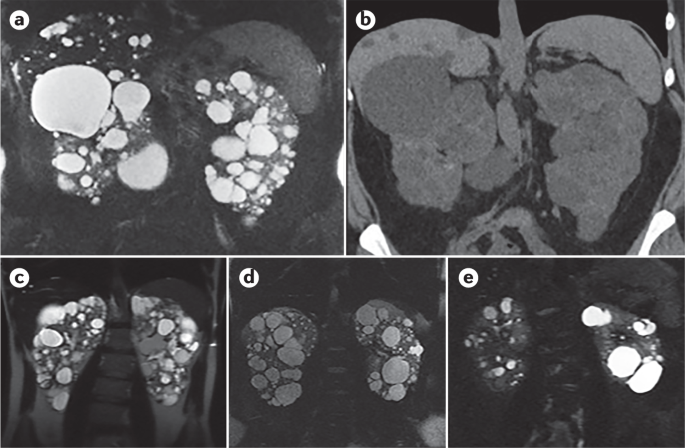

Abdominal CT scan of an adult with autosomal dominant polycystic kidney disease. Urinary incontinence or retention. CT scans of the kidney may be used to evaluate the back part of the belly.

Figure caption and citation for the preceding image starts. Find this Pin and more on Health by Gable Rhoads. Autosomal dominant polycystic kidney disease ADPKD is characterized by progressive renal enlargement and renal failure.

Role of Multislice CT Scan. Polycystic kidney disease isnt limited. An image-based classification system based on total kidney volumes from CT scan has been used to identify potential cases of more rapidly progressive disease.

Autosomal Dominant Polycystic Kidney Disease Radiology Case Radiopaedia Org